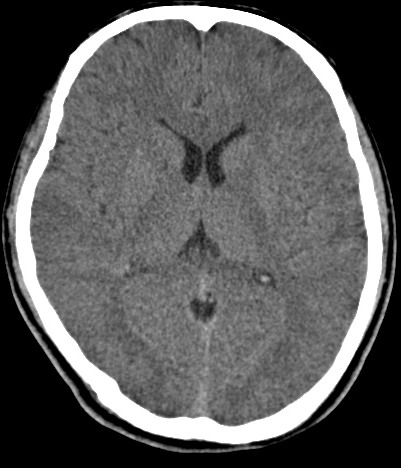

男,31岁,头疼就诊,其他不祥。

考虑右颞叶脑血管畸形伴出血。avm可能大,建议dsa。

平扫见右颞叶、右侧脑室后角旁略高密度影,增强未见明显病灶,基本正常。不放心做mri检查

病灶呈略高密度,周围伴环形水肿,无强化/无异常av影........

考虑为:1.脑内小血肿?   2.脑灰质异位?   建议mri检查........

考虑右颞叶脑血管畸形伴出血。考虑静脉血管瘤,深部型的,avm不除外,建议dsa。